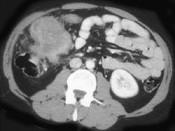

男,42岁,左下腹可触及一长条形肿块,结合图像,最可能的诊断是()A.结肠间质瘤B.结肠转移瘤C.结肠淋巴瘤D.假膜性肠炎E.结肠癌

问题 男,42岁,左下腹可触及一长条形肿块,结合图像,最可能的诊断是()

选项 A.结肠间质瘤 B.结肠转移瘤 C.结肠淋巴瘤 D.假膜性肠炎 E.结肠癌

答案 C